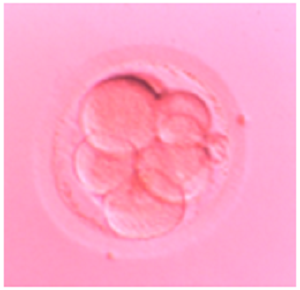

Human day 2 embryo generated in a SYNTHETIC PROTEIN-FREE (ART-7b) MEDIUM (fertilization up to day 2). Embryo transfer (n=3) was performed on day 2. The ART-7b medium has been phased out. This embryo is now a young man in his early twenties, one of a set of triplets (all boys). This was the first report of the successful generation of human embryos in a completely synthetic medium devoid of donor serum proteins. (Proc. XVI Ann. Sci Meeting Fertil Soc Australia, 2-4 Nov, 1997, Adelaide, Australia, p.34; Ali et al., Human Reprod 15:145, 2000).